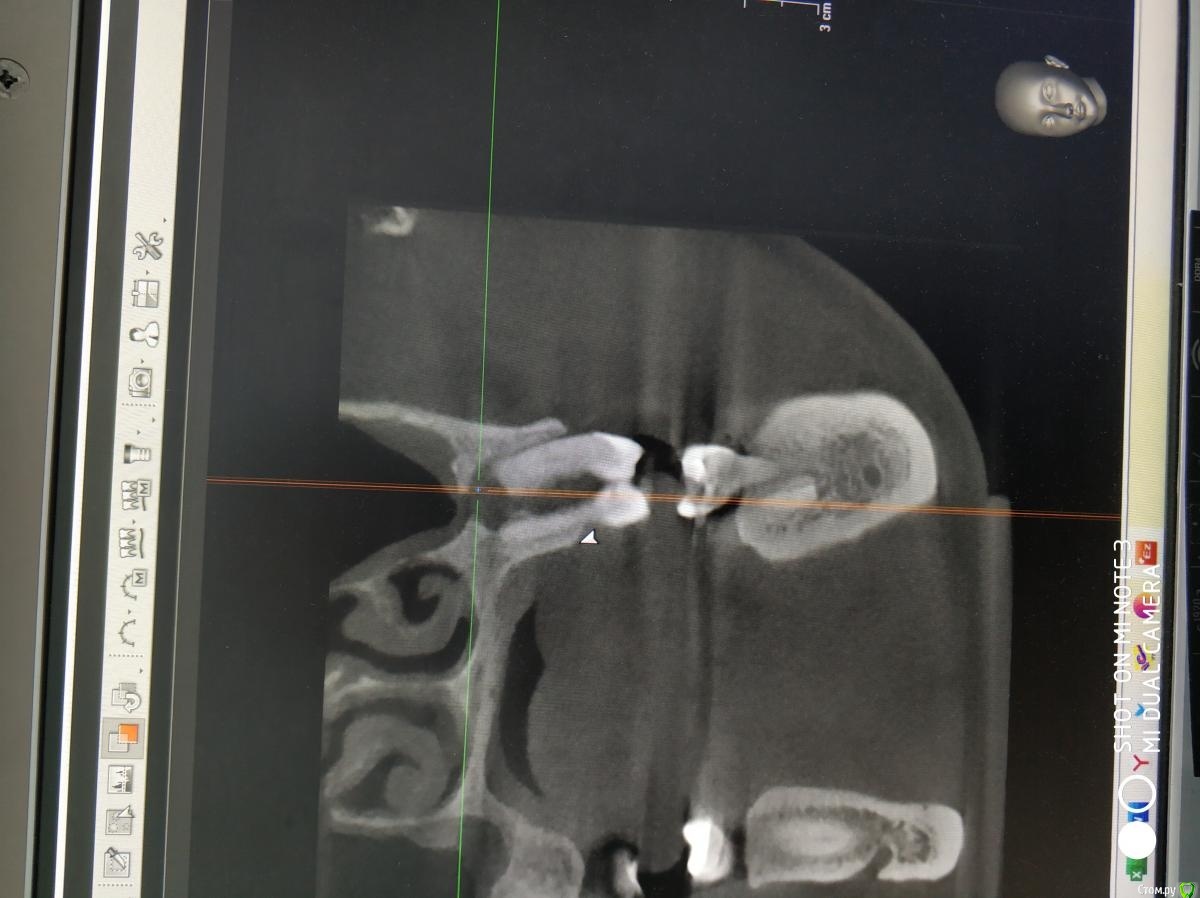

It'sGeorgy Опубликовано 20 февраля, 2021 Поделиться Опубликовано 20 февраля, 2021 А что именно смущает? Что дефект с пазухой сообщается? Так закроете после удаления, ничего страшного. ЛОРу, имхо, там делать нечего пока еще.Недавно был подобный случай: А вообще, судя по тем скринам, которые вы выложили, я бы пациента терапевтам показал для начала. Ссылка на комментарий

Raystom Опубликовано 20 февраля, 2021 Автор Поделиться Опубликовано 20 февраля, 2021 А что именно смущает? Что дефект с пазухой сообщается? Так закроете после удаления, ничего страшного. ЛОРу, имхо, там делать нечего пока еще.Недавно был подобный случай:12.png23.png22.png А вообще, судя по тем скринам, которые вы выложили, я бы пациента терапевтам показал для начала.Именно, что с пазухой. С терапевтами общались, при попытке препарирования зуб "мягкий", как кариозный судя по их словам Ссылка на комментарий

It'sGeorgy Опубликовано 20 февраля, 2021 Поделиться Опубликовано 20 февраля, 2021 Именно, что с пазухой. С терапевтами общались, при попытке препарирования зуб "мягкий", как кариозный судя по их словамну так закроете По поводу способа закрытия скажу вообще непопулярное мнение: я бы просто затромбовал колаполом, дал небольшую подвижность вестибулярному лоскуту и сопоставил края монофилом. Знаю, что это не всегда срабатывает, но меня пока проносило, уже раз 20. Дефект, который сверху выкладывал, закрыл таким же способом. Если недостаточно опыта(как у меня и было), возиться с VIP-CT - не лучшая идея. А вообще, не факт, что там будет ОАС. Часто бывает, что между лункой и пазухой есть тонкая костная пластинка, которой просто на снимке не видно. Ссылка на комментарий